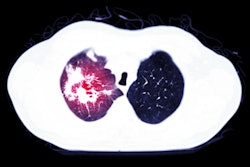

To investigate their hypothesis, researchers analyzed mortality rates for 129 hospitalized COVID-19 patients in Wuhan, China, and 251 patients at King’s Health Partners in South London, treated between February and May 2020. All patients had echocardiography on hospital admission, and the average patient age was 58.

The authors compared the echocardiography results of COVID-19 patients with those of adult patients with otherwise similar health profiles who had an echocardiography test before the pandemic. First-phase ejection fraction was measured with conventional echocardiography imaging conducted at the bedside of hospitalized patients.